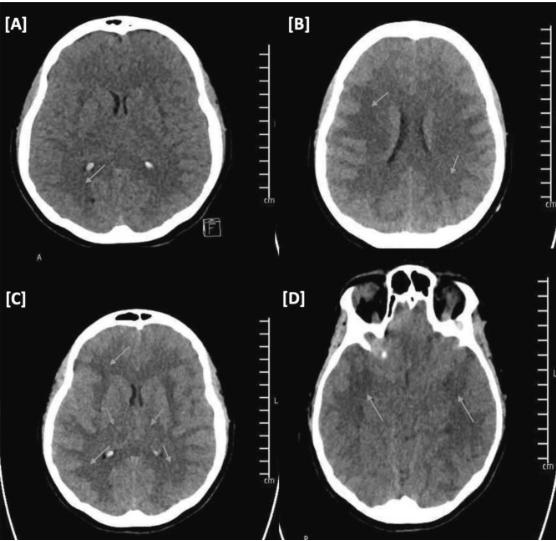

图1、CT头部无对比增强

(A)初始CT头颅:存在全身性脑水肿和弥漫性白质低密度。(B-D)12小时后CT头部:全身性脑水肿显著进展。累及大脑和小脑的弥漫性白质低密度。双侧丘脑低密度

紧急复查头部CT(图一B-D)显示新出现的弥漫性低密度白质,累及大脑、小脑和双侧丘脑,伴有明显的全身性脑水肿,伴有鞍上池的闭塞,提示双侧颞叶沟回疝形成。初步诊断为暴发性ADEM(急性脱髓鞘性脑脊髓炎)。经神经外科会诊,建议不进行手术干预。患者管理包括多学科方法和结构化的支持医疗护理和标准颅内压指导措施。由于初步诊断为暴发性ADEM,患者开始静脉注射甲基强的松龙1g/d, 3%高渗生理盐水,连续5天,参数为颅内压升高1级和2级。